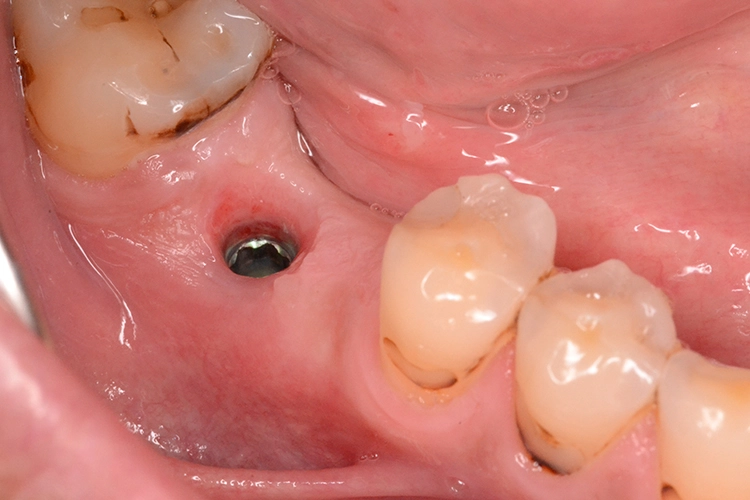

5. Multiple Sofortimplantationen in Zusammenhang mit internem Sinuslift

Beim vorliegenden 54-jährigen Patienten mussten aufgrund von lokaler Parodontitis die Zähne 25, 26 und 27 entfernt werden. Im apikalen Bereich lag jedoch gesunder Kieferknochen vor, sodass eine Sofortimplantation möglich war. Aufgrund der guten Einsichtbarkeit des Operationsgebietes nach Zahnextraktion konnte in diesem Fall flapless vorgegangen werden.

Dr. Plöger

In regio 26 konnte das Implantat dabei komplett apikal im gesunden Knochen verankert werden. In regio 27 jedoch wurde lediglich eine Restknochenhöhe von 8 mm bestimmt. In diesem Fall wurde die Sofortimplantation mit einer internen Sinusbodenelevation nach Summerset kombiniert.

Da zur Aufweitung der Trifurkation die Densah Versah Burs im Rückwärtslauf eingesetzt wurden, kann durch die Osseodensifikation auch der Kieferhöhlenboden bis zu einem bestimmten Umfang mit dieser Technik der Knochenverdrängung angehoben werden. Wird die Kieferhöhle tatsächlich eröffnet, kann auch Knochenersatzmaterial durch den Bohrstollen in die Kieferhöhle augmentiert werden, unter der Voraussetzung einer intakten Kieferhöhlenmembran.

Aufgrund der Rückwärtsdrehung der Bohrer ist die Perforationswahrscheinlichkeit der Membran jedoch nicht höher als bei konventionellen Verfahren. Sollte die Membran tatsächlich perforiert werden, muss gegebenenfalls auch eine externe Sinusoperation mit Verschluss des Membrandefektes angeschlossen werden.